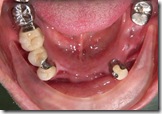

患者A先生

上顎 正面 下顎

患者B小姐

以上兩位患者口內狀況非常複雜,要制定一個好的治療計畫,

不只要考慮到患者的牙齒條件,

還要顧及患者意願、時間、金錢、評估可獲得的結果等等。

所以像這類型的Case 醫師通常在初步的溝通後會先做出一兩個不同的治療計畫,

再和患者解釋,了解患者接受程度。